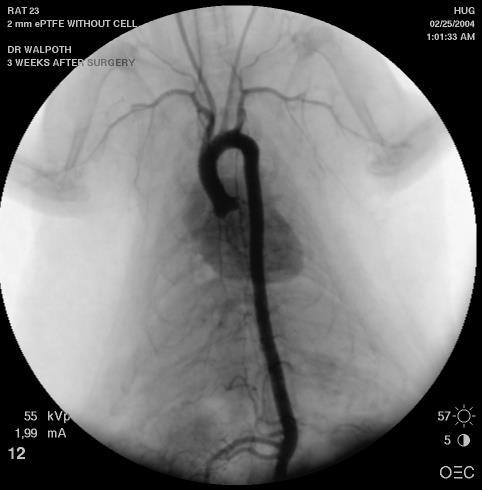

Currently, there is no commercial small calibre vascular prosthesis (internal diameter less than 6 mm) for surgical revascularisations due to poor clinical patency results caused by early thrombosis and late intimal hyperplasia (Abbaszadeh et al , Halbert et al ) We have therefore developed an anti-thrombogenic and cell-favouring Layerby-Layer (LbL) coating

Our dual-action coating is based on end-point attached heparin and cellfavouring LbL coating The coating was applied to small calibre, micro-porous, degradable polycaprolactone (PCL) electro-spun vascular grafts and patches and compared to uncoated samples In vitro coagulation tests (thrombin time / partial thrombin time / anti-Xa assays) and thrombin generation tests up to 7days were made

The in vitro coagulation tests showed no coagulation, and the thrombin generation assay showed no clot formations up to 7-days on the coated patches, compared to thrombus formation (high levels of EPT (nmol/l/m)) for the uncoated patches There was a higher endothelial cell proliferation on the coated patches at 7-days in cell culture as well as a reduction of smooth muscle cells

and 12-weeks (n = 3 per coating and implantation duration) PRE-CLINICAL OUTCOME DATA

This novel dual-action coating has shown good in vitro and in vivo anti-thrombotic and endothelial cell proliferating effects on micro-porous, degradable, vascular grafts.

Application of our coating on clinically used ePTFE grafts show similar promising results in vitro Thus, it could show benefits in clinical revascularization operations such as: coronary, peripheral

Therefore, small calibre, shelf-ready, vascular prostheses are needed as alternatives to autologous grafts for better clinical outcomes A lot of research emphasizes the possibility of using tissue-engineered vascular grafts (Mallis et al ) Therefore, we elected to use a biodegradable small calibre vascular graft for our coating

Degradable vascular graft characteristics